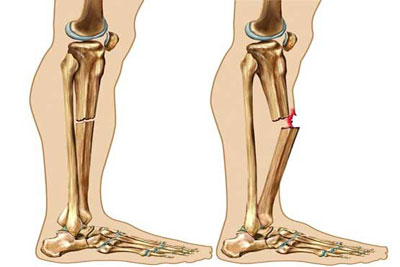

این سرطان در سنین زیر 20 سالگی رخ می دهد و احتمال ابتلاء به آن با افزایش سن کم می شود. درمان سرطان استخوان انتخاب روش درمان بستگی به نوع اندازه مرحله سرطان سن و سلامت عمومی بیمار دارد. سرطان استخوان چیست انواع سرطان استخوان. چشم انداز بهبود سرطان استخوانی بستگی به عواملی مانند سن نوع سرطان استخوان گستردگی سرطان مرحله و احتمال گسترش بیشتر آن درجه دارد به طور کلی در مورد سرطان استخوان بسیار ساده تر است که.

تشخیص سرطان استخوان. استئوسارکوم شایع ترین نوع است که بیشتر بر کودکان و نوجوانان زیر 20 سال تأثیر می گذارد. جراحی اغلب اولین انتخاب درمانی می باشد اگرچه گاهی اوقات قطع کردن عضو لازم می باشد. درمان سرطان استخوان به نوع سرطان بستگی دارد.